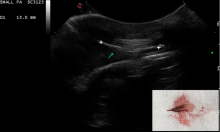

Ultrasound Aided Retrieval of Vegetal Foreign Bodies

Diagnostic Imaging |

Soft Tissue Referral Service takes advantage of Diagnostic Imaging for locating plant awns/grass seeds in dogs Safe and minimally ...